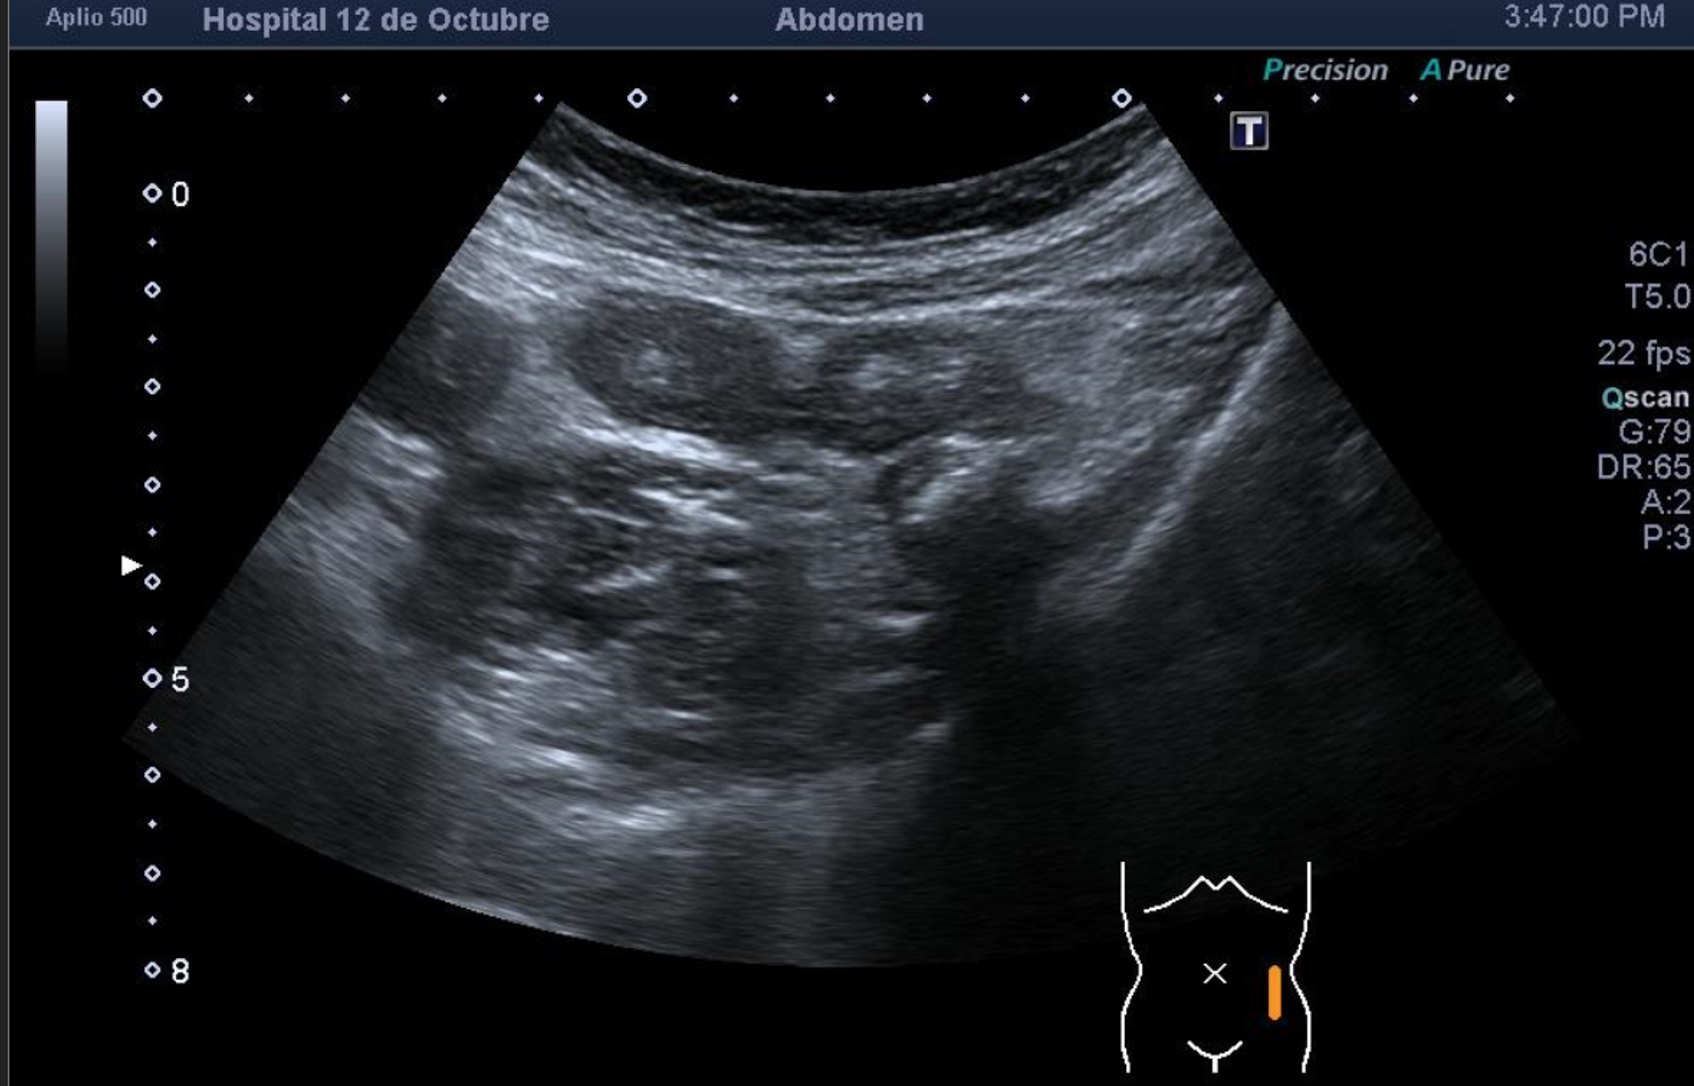

También se realiza ecografia en urgencias del hospital.

En el hospital se realiza una nueva ecografía en el servicio de radiología confirmando el diagnóstico de sospecha: diverticulitis aguda en sigma distal sin datos de complicación. Hinchey 1A.